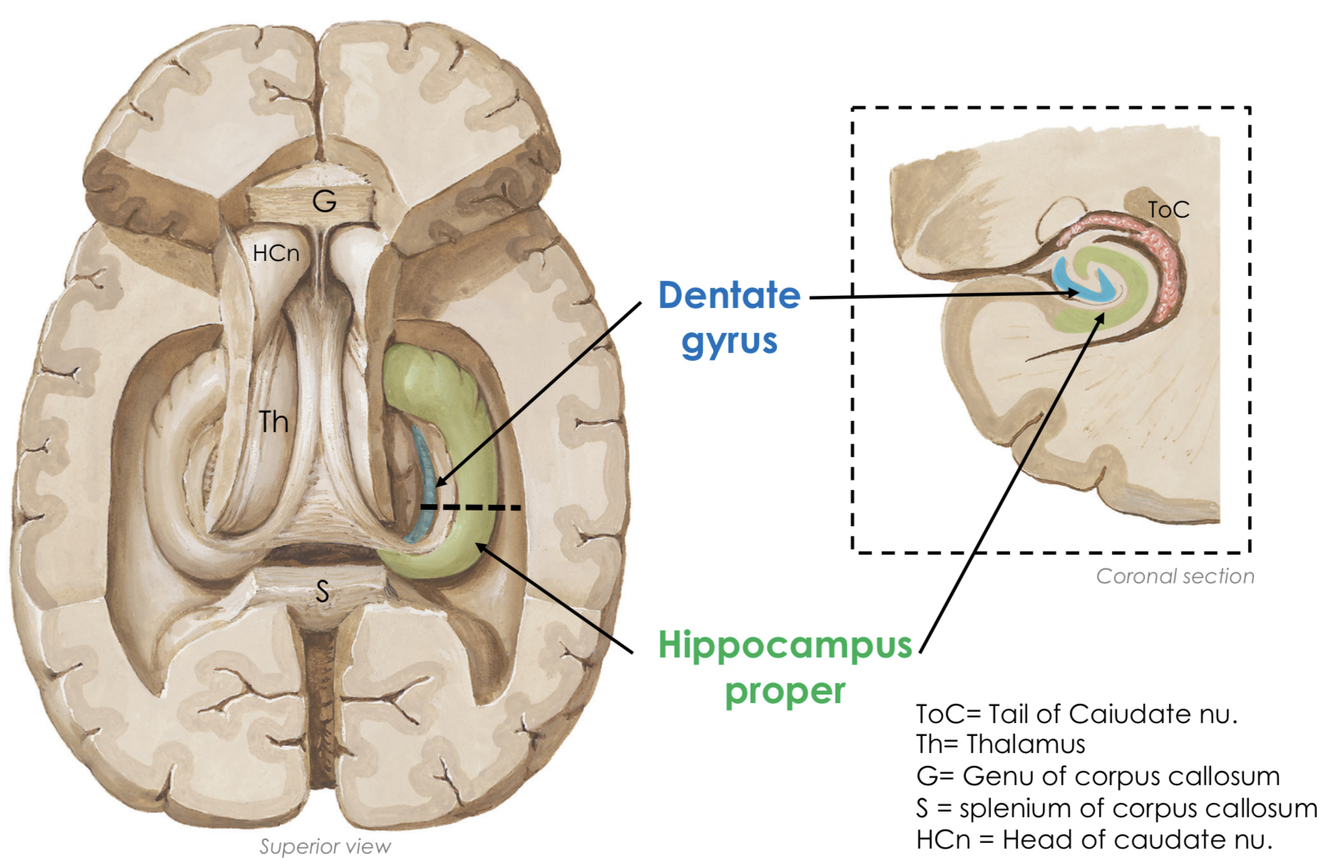

Label the features of the hippocampal formation

What is their appearance like?

Dentate gyrus:

- strip of grey matter with a tooth-like appearance

Hippocampus proper:

- has a seahorse appearance in coronal section

the hippocampal formation forms the floor of the inferior horns of the lateral ventricles